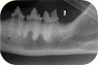

Als Gründungspräsident der ÖGTZ (www.oegtz.at) wird die Zahnheilkunde für ihre Tiere auf dem neuesten Stand angeboten; natürlich auch mit digitalem Dentalröntgen, um eine auf guter Diagnostik basierende Zahnbehandlung zu gewährleisten!

Seit 2007 erfolgt die Röntgenbildentwicklung (Großbildröntgen sowie intraorale Zahnröntgen) mit einem modernen digitalem System, womit die Röntgenbelastung ihres Tieres vermindert wird. Zudem sind wir eine anerkannte HD-Röntgenstelle des SVÖ. Seit 2022 3D Bildgebung im Kopfbereich: CB-CT (DVT).